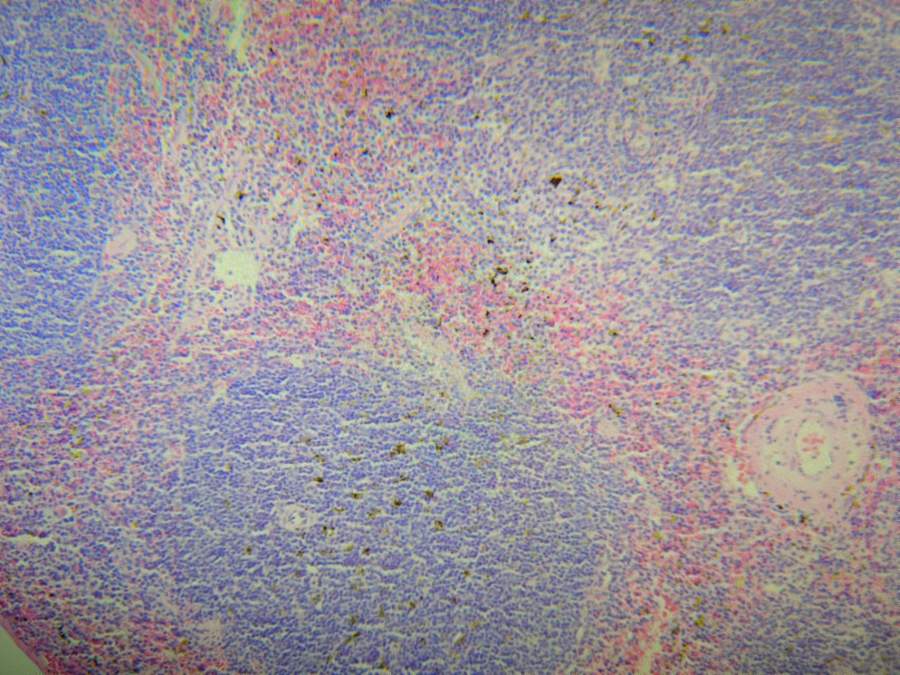

×î½ü×öÁËÆ¢ÔàheȾɫ£¬·¢ÏÖÓлÆÉ«ÔÓÖÊ£¬ÆäËû¼¸¸öÔàÆ÷Ò»ÆðȾµÄ¶¼Ã»ÓУ¬°ÑÊ÷Ö¬Óöþ¼×±½Ï´µôÁËÔÓÖÊ»¹ÔÚ£¬Ó¦¸Ã²»ÊÇÊ÷Ö¬ÎÊÌâ¡£ÏëÎÊÎÊ´ó¼ÒÓгöÏÖ¹ýÕâÖÖÇé¿öÂð£¬ÊÇÔõô´¦ÀíµÄ![]() ![]() ΢ÐÅͼƬ_20231103224710.jpg |